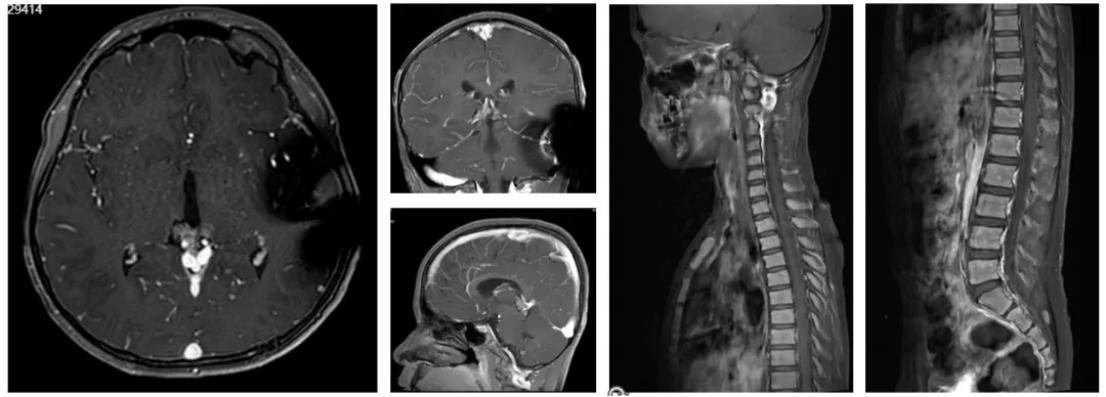

2023年10月7日患者无诱因出现恶心、呕吐、精神差,肢体乏力,无视物模糊、视物缺损等症状入院,并于10月12日和16日进行MR和CT检查(图3-4),结果提示:肿瘤复发并梗阻性脑积水。

图3 复发后MR检查

术后第一天(10月17日),患者体格检查显示,昏迷—嗜睡,双侧瞳孔D=3.0mm,光反应(+),CT检查结果提示脑积水缓解(图5)。术后血清和脑脊液肿瘤标志物检测(图6)、脑脊液细胞学检查和全脊髓MRI检查均为阴性。临床诊断为松果体区复发生殖细胞瘤,梗阻性脑积水。

术后第二天(10月18日)给予患者抢救性化疗(EP方案:顺铂24mg d1-3+替尼泊苷60mg d4-6),化疗期间患者无过敏及其他不良反应,且神志由昏睡转为清醒,可配合问答、遵嘱完成动作。2023年11月9日化疗1个疗程后,MR检查提示肿瘤明显缩小(图7),且患者神志清醒,血清、脑脊液肿瘤标志物及脑脊液细胞学检查均为阴性。综合各项结果显示,肿瘤部分缓解(PR)。化疗4个疗程后(2023年10月-12月),MR检查提示原发肿瘤明显缩小,无脊髓播散证据(图8),患者肿瘤接近完全缓解(CR)。

图7 化疗1个疗程后,MR检查

图8 化疗4个疗程后,MR检查